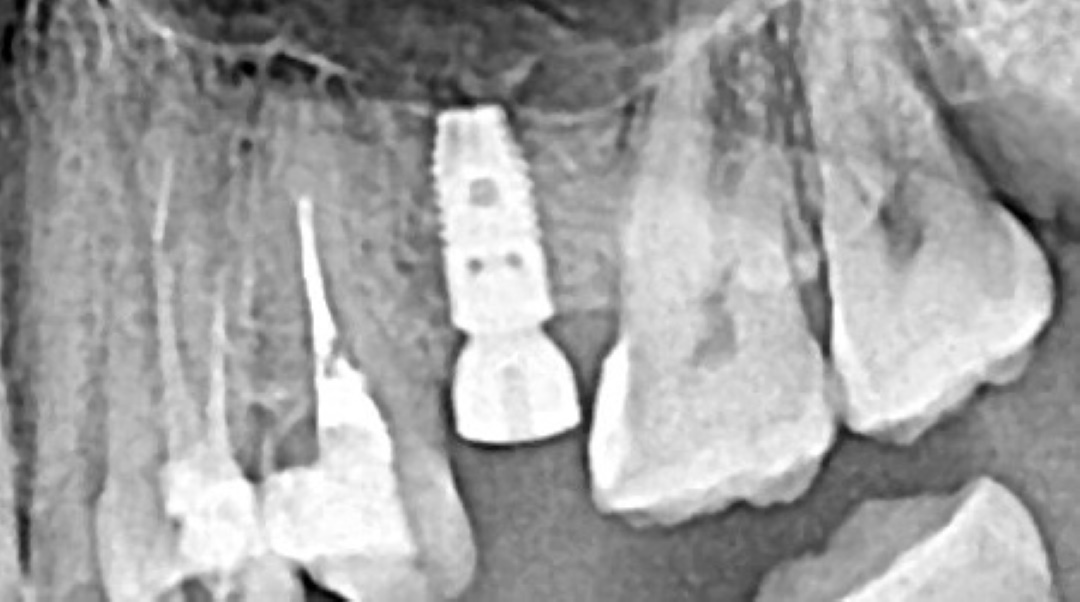

Спустя три месяца мы получили полное восстановление костной ткани. Мы установили 4 импланта в позиции 13, 14, 16, 17. Сразу были установлены формирователи десны.

Спустя три месяца вы видим отличный результат как на рентген снимке, так и на фото. Объема слизистой достаточно для начала ортопедического этапа.